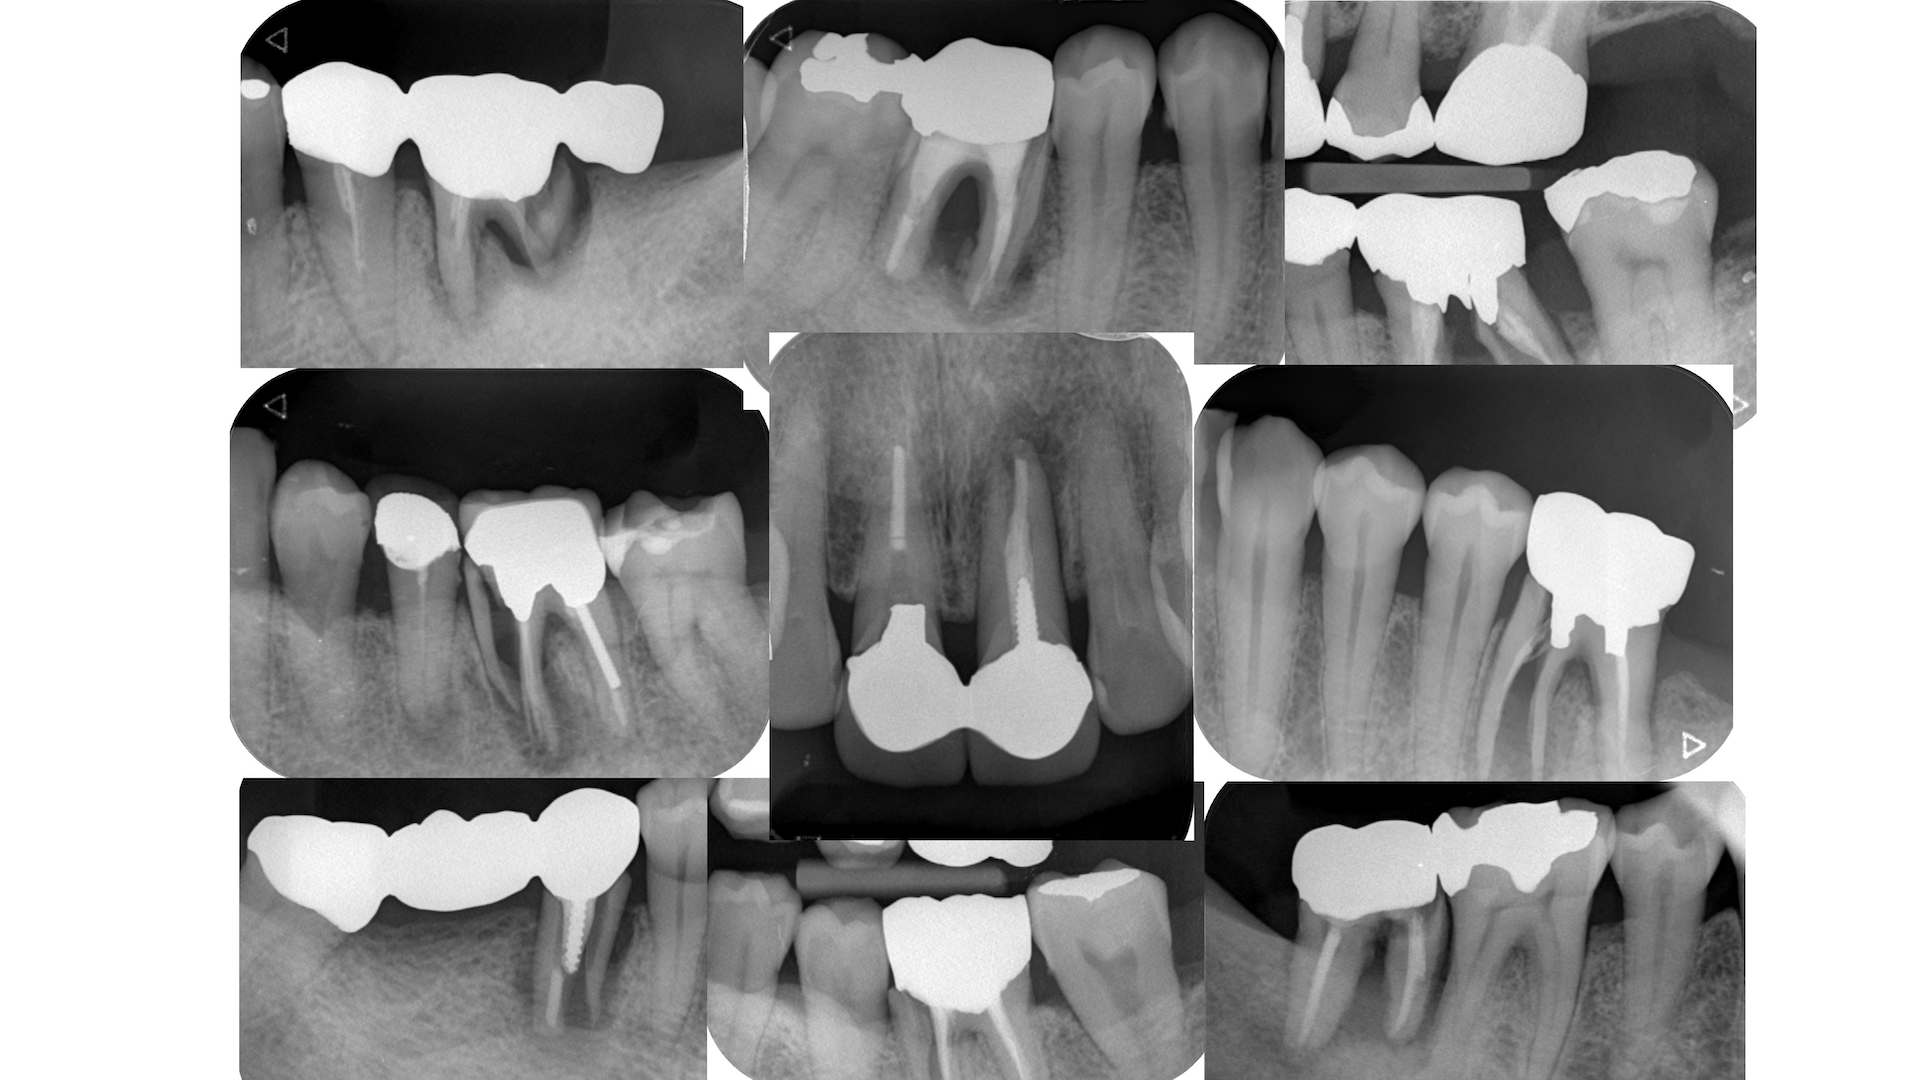

また、歯根が割れる場合も歯科治療にはある。

以下だ。

これらに共通することは何だっただろうか?

根管口部が過剰に削られた歯、

根管自体を回転切削器具で削った歯、

側方加圧でスプレッダーでグイグイやった歯はもれなく破折してしまう。

これらは全て

医原性だ、と言うことを臨床家は肝に銘じておくべきだろう。

その末路が、以下だ。